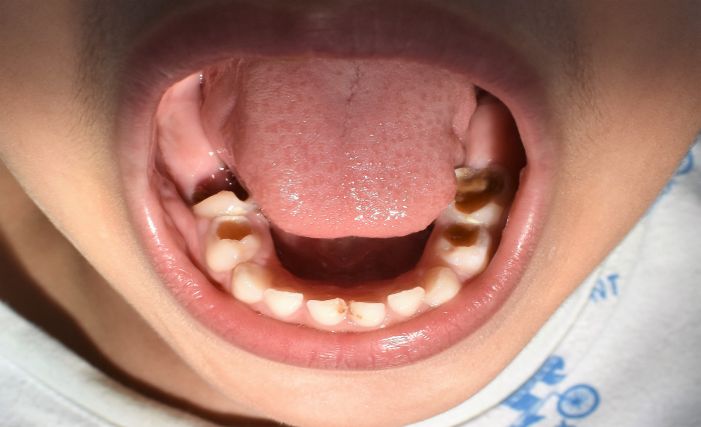

Es una enfermedad que afecta a los niños en sus primeros años de vida y compromete particularmente los dientes de la primera dentición (dientes de leche o dientes temporales) y en algunos casos logra la afectación de los primeros dientes permanentes que empiezan a aparecer hacia los 6 años.

La enfermedad se caracteriza por una destrucción rápida y masiva de estos elementos dentales generando dolor, incapacidad para comer, para hablar para deglutir y si no hay un tratamiento adecuado y a tiempo, los estadios de la enfermedad avanzan y las infecciones se establecen en la cavidad oral y en muchos casos se diseminan a otros sitios de la boca e inclusive de partes del cuerpo diferentes a la cavidad oral.

La caries de la infancia temprana puede ser causante de perdida prematura de la dentición temporal, y esta condición dada por grandes destrucciones o infecciones producidas por la enfermedad, causa otra gran cantidad de problemas en la salud general de los niños, su bienestar se ve muy afectado, su capacidad de masticar, de hablar, de socializar, de procesar adecuadamente los nutrientes que le aporta su alimentación.